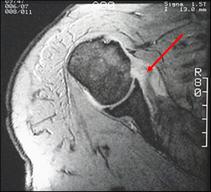

Supscapularis tendon rupture

Normal tendon